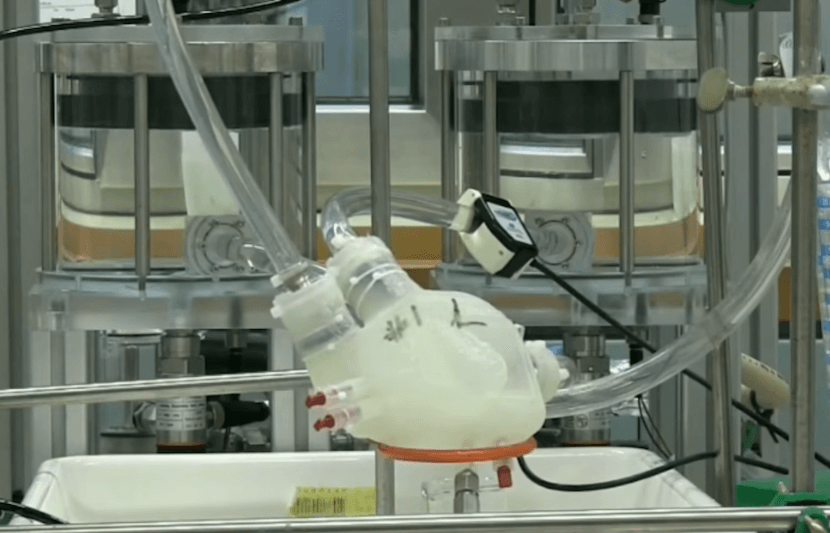

ETH Zurich Researchers Develop Soft Artificial Heart Using 3D-Printing Method and Silicone

Heart failure is a major problem afflicting about 26 million people around the world. In the U.S. alone, about 6.5 million people suffer from heart failure, and the the number is projected to rise to 8 million by 2030, according to the American Heart Association. When heart failure reaches end stage, heart transplant may be… Read More